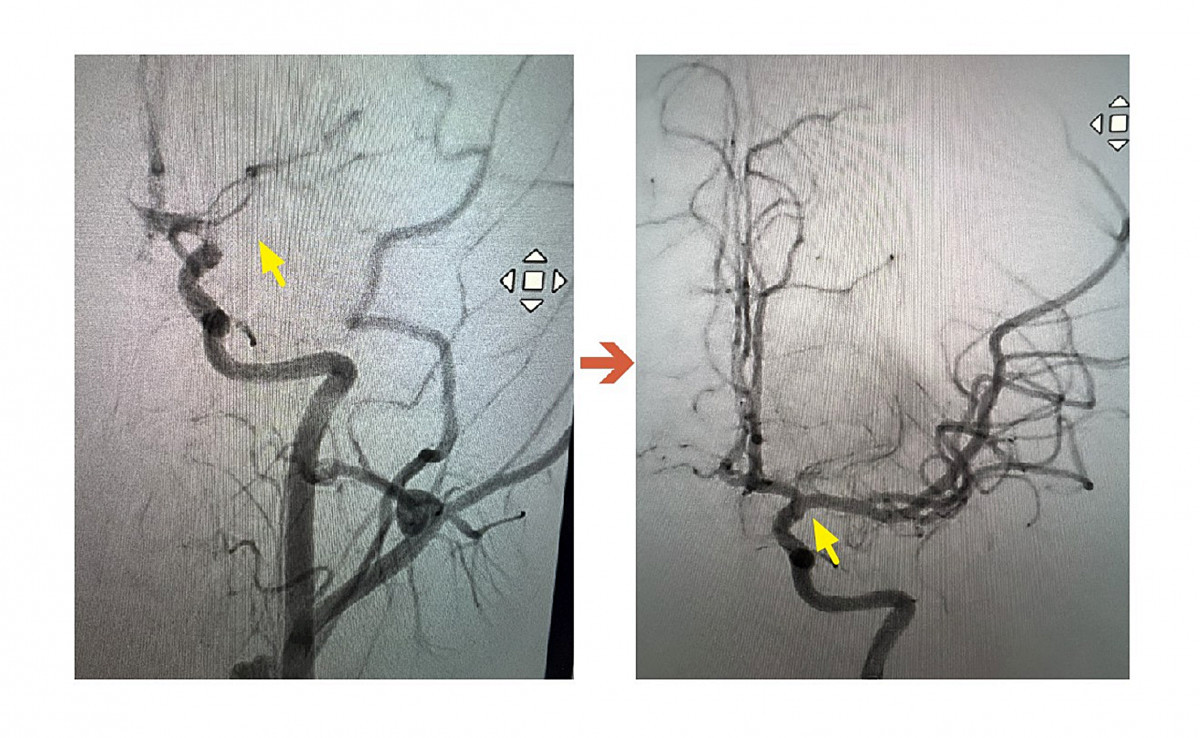

影像檢查結果出爐後,神經內科李振華醫師迅速判讀,確定為左側中大腦動脈栓塞造成缺血性腦中風。在與家屬充分溝通後,影像醫學科主任暨取栓醫師郭葉璘隨即與取栓團隊進行急性腦中風顱內動脈血栓移除(Intra-arterial thrombectomy, IAT),並從腹股溝導引導管至左側中大腦動脈阻塞處,採用強力抽吸方式清除血栓。手術從開始到打通血管僅約10分鐘,成功取出4個血栓,最大達1.1公分。術後患者血流恢復暢通。

ICA血管攝影,圖左箭頭處為血栓阻塞血管。圖右箭頭處為已打通血管。